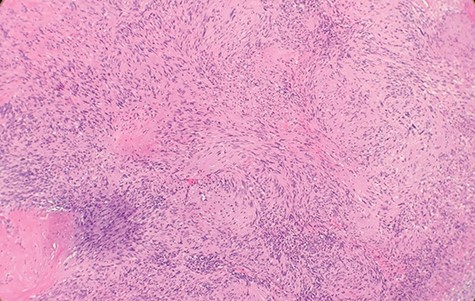

Macroscopically, the tumor appeared encapsulated, rubbery and pink-tan in color. Microscopic examination reveals that tumor composed of biphasic spindle hypercellular Antoni A areas and hypocellular Antoni B areas (Fig. 1). Higher magnification reveals that spindle tumor cells are narrow, elongate, wavy with tapered ends interspersed with collagen fibers (Fig. 2). Immunohistochemical staining revealed that most tumor cells reacted strongly for S-100 protein (Fig. 3). Combined with immunohistochemical profile, these histological features are diagnostic of benign schwannoma. Patient was discharged home on the same day as the operation. At the 1-month follow-up, he was symptom free, without any pain or sensory disturbances.

Immunohistochemical staining revealed that tumor cells are strongly positive for S-100 protein (×40).